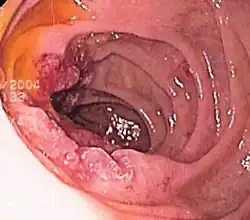

Cáncer de hígado

El alcohol es un factor de riesgo de cáncer de hígado, a través de la cirrosis.[71][72][73]"La cirrosis es el resultado de la formación de cicatrices dentro del hígado, en la mayoría de los casos debido al consumo crónico de alcohol".[74]

"Aproximadamente el 5% de las personas con cirrosis desarrollan cáncer de hígado. La cirrosis es una enfermedad que se desarrolla cuando las células del hígado son sustituidas por tejido cicatricial tras sufrir daños por el abuso del alcohol,... "[75]

El NIAAA informa que "el consumo excesivo y prolongado de alcohol se ha asociado en muchos casos con cáncer de hígado primario". Sin embargo, se cree que es la cirrosis hepática, ya sea causada por el alcohol u otro factor, la que induce el cáncer".[76][77]

"Las probabilidades de padecer cáncer de hígado aumentan notablemente con cinco o más copas al día" (NCI).

Un estudio concluyó que por cada bebida adicional consumida regularmente por día, la incidencia de cáncer de hígado aumenta en un 0,7 por 1000.[42]

En los Estados Unidos, el cáncer de hígado es relativamente poco común y afecta aproximadamente a 2 personas de cada 100 000, pero algunos investigadores relacionan el consumo excesivo de alcohol con hasta el 36 % de estos casos.[27][78] "En general, el 61 % de los CHC se atribuyeron al VHC [virus de la hepatitis C], el 13 % al VHB [virus de la hepatitis B] y el 18 % al consumo excesivo de alcohol".[79] Un estudio en la provincia de Brescia, en el norte de Italia, concluyó: "Según los riesgos atribuibles a la población (RA), la ingesta excesiva de alcohol parece ser la causa más importante de CHC en esta zona, seguida de la infección por el VHC y el VHB .[80]